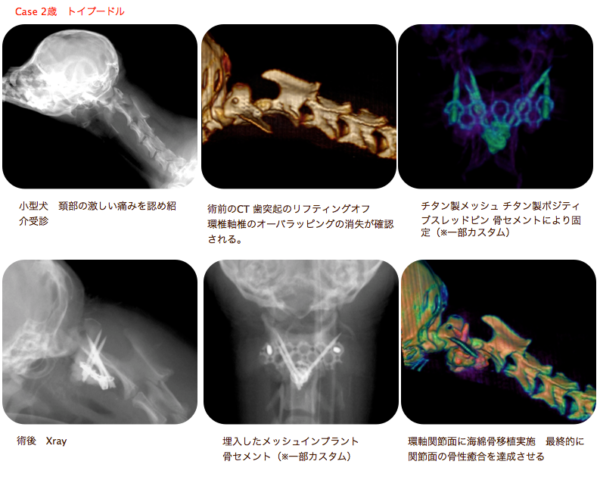

環軸不安定症 AAI

AAIとはヨークシャーテリア、チワワなどの超小型犬に発症する第一頚椎と、第二頚椎の不安定性による頸髄の障害です。通常、頚部痛、四肢不全麻痺などの症状がでます。

悪化すれば呼吸停止により突然死することもあります。